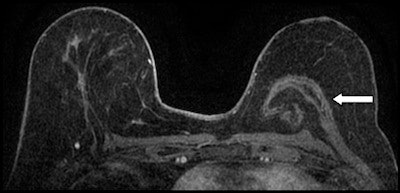

Reconstruction with latissimus dorsi myocutaneous flap: Latissimus dorsi muscle, fat and skin are rotated to reconstruct the breast. Top: Sagittal fat-saturated T1-weighted image shows latissimus dorsi muscle flipped anteriorly for reconstruction (white arrows) and the denuded dermal layer is seen parallel to the chest wall (white arrow heads). Bottom: Axial fat-saturated T1-weighted subtraction image with postcontrast gadolinium injection, the flap consisting of the latissimus dorsi muscle and its overlying skin and fat flipped and tunneled from the back to the neobreast (white arrow), giving a tailed appearance to the muscle in the lateral breast. This can be used as a differentiator on imaging from transverse rectus abdominis myocutaneous (TRAM) flap reconstruction. All images courtesy of Dr. Vandana Dialani.